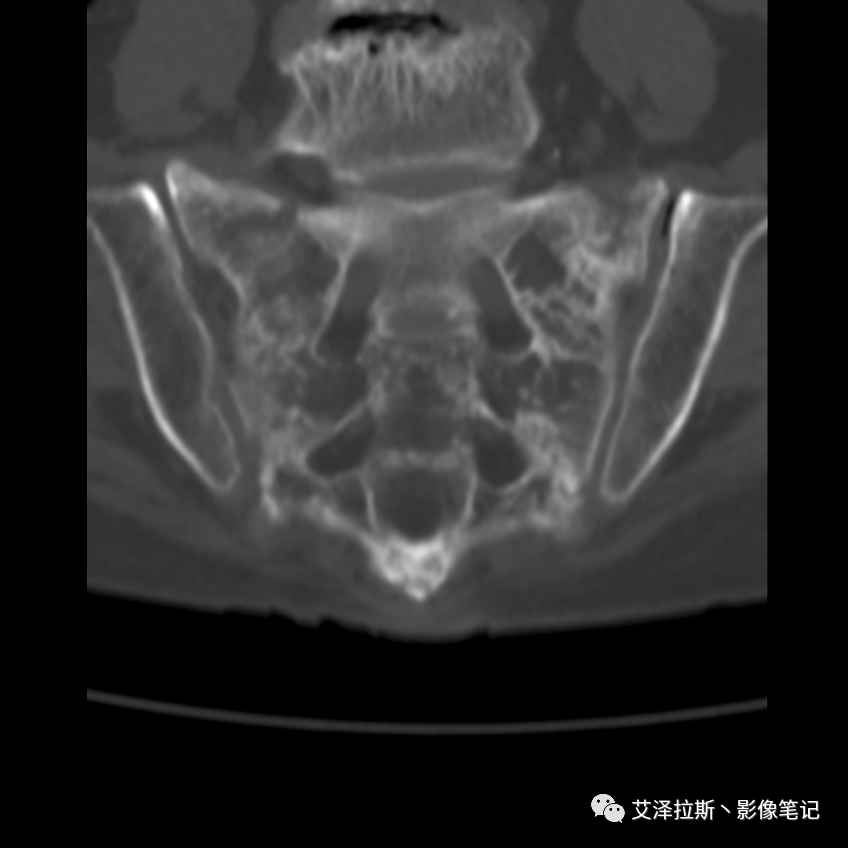

病例2:患者,女性,69岁,老年性骨质疏松症。

CT平扫:

X线、CT:骶骨重度骨质疏松,双侧骶骨翼皮质断裂,分别见迂曲走行的纵行透亮线位于骶孔外侧,大致与骶髂关节间隙平行,骨折端局部可见骨痂、骨质硬化。

骶骨功能不全骨折

①单侧或者双侧骶骨翼骨折,典型者呈“H”形,即“Honda征”;

②骨折线位于骶孔外侧(如下图,主要发生于1区),通常可能会伴随耻骨的功能不全骨折(如:病例2 右侧耻骨上支骨折,L5双侧横突骨折);

③愈合期骨折线模糊,骨痂形成,骨质硬化;